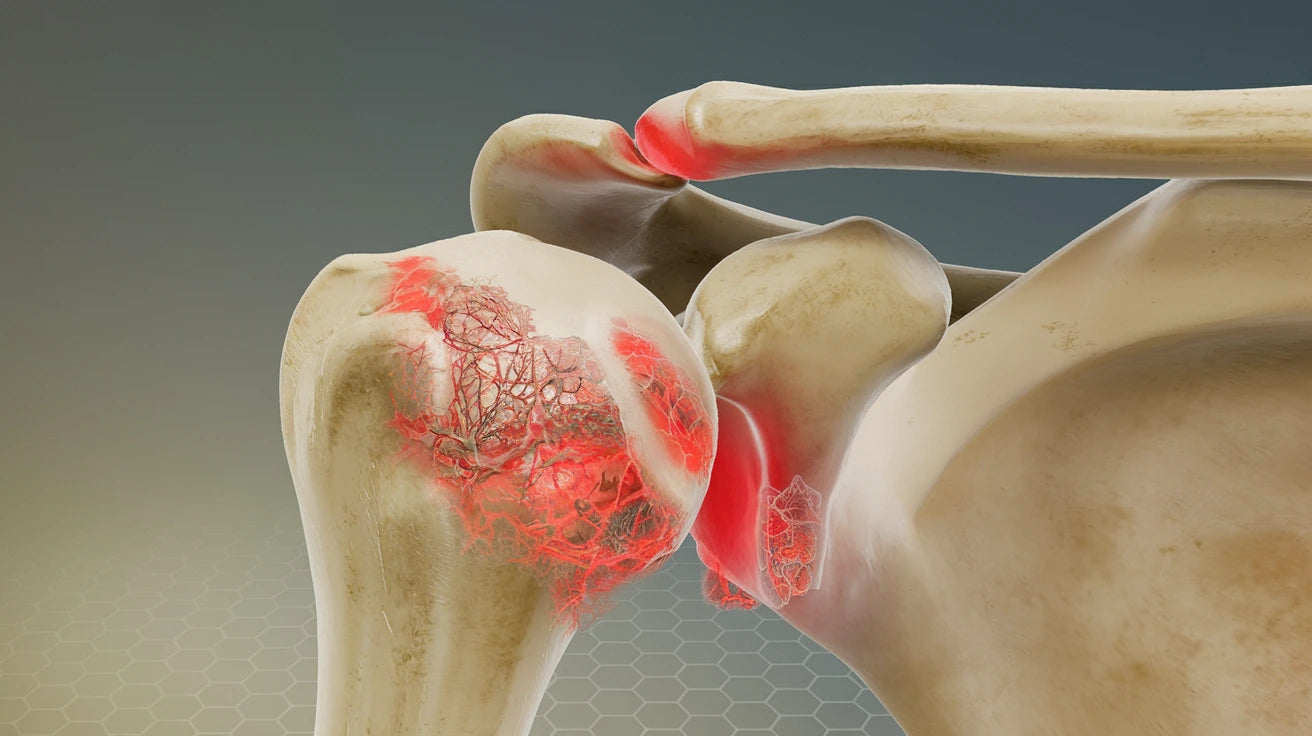

Axelleden är en av kroppens mest rörliga leder – men också en av de mest utsatta. Smärta i axeln kan bero på inflammation, överansträngning eller ledförslitning. Lär dig mer om olika axelproblem och hur du kan lindra dina symtom.